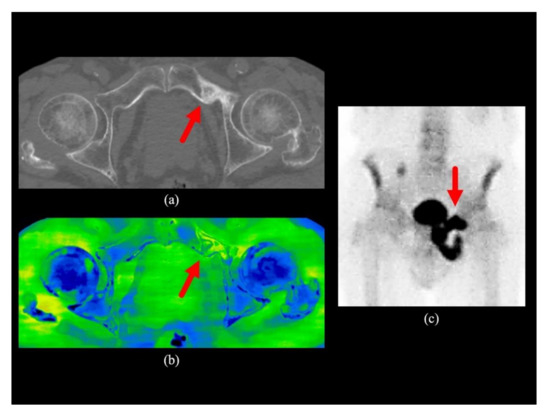

| 2 | Do not qualify as score 1, 3, 4, or 5 | Do not qualify as score 1, 3, 4, or 5 on conventional CT images. Water-HAP images show a focal asymmetric density lower than skeletal muscle but higher than surrounding bone marrow, but conventional CT images do not indicate any abnormalities |

| 3 | Ill-defined solitary sclerotic or lytic lesion | Ill-defined solitary sclerosis or lytic lesion on conventional CT images, or water-HAP images show focal asymmetrical density equal to or higher than skeletal muscle, but no abnormal density was found on conventional CT images |